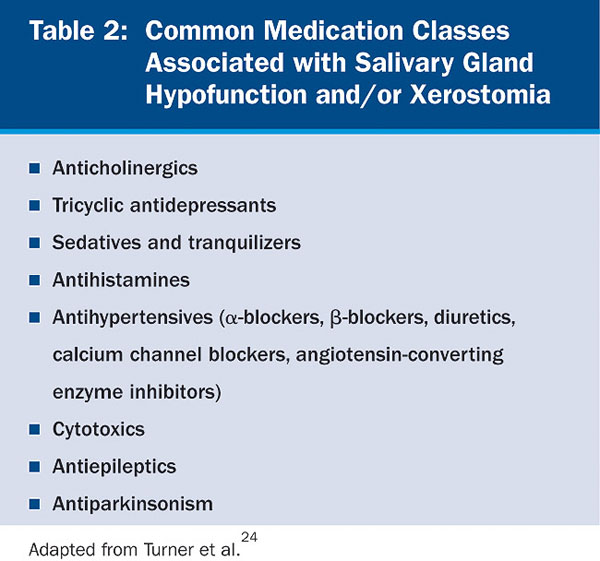

Aging per se has no significant impact on salivary gland secretion.12 In the elderly, several factors, such as decrease of ptyalin, increase of mucin, and low stimulation of the peripheral receptors, have been implicated in xerostomia.13 Xerostomia and/or salivary gland hypofunction in this population has been associated with a number of systemic disorders (Table 1) and medications14,15 (Table 2). The incidence increases with medication exposure,16 with more than 400 drugs implicated.2 In a 5-year longitudinal study, the relationship of dry mouth and long-term exposure to medications was assessed. Xerostomia severity was found to be higher among females and associated with the use of medications, such as antianginal, diuretics, antidepressants, and antiasthma, as well as thyroxine.17 Xerostomia and salivary gland hypofunction are also major complications of radiation or chemotherapy. Long-term morbidity in patients receiving combined radiation and chemotherapy is significant because of xerostomia, salivary gland hypofunction, and severe dysphagia.18